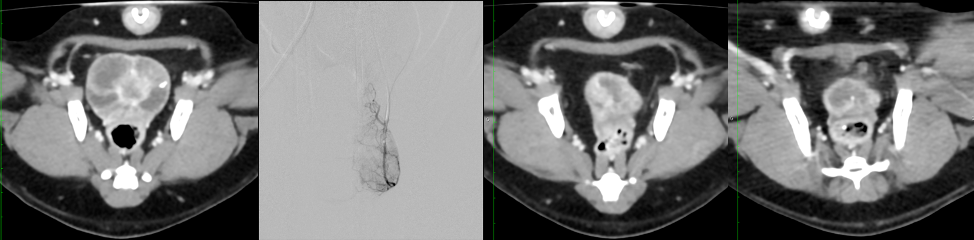

Interventional Oncology (IO) is a subspecialty field of Interventional Radiology (IR) that deals with the treatment of cancer and cancer-related problems using targeted minimally invasive procedures performed under image guidance. IO has successfully established itself as an essential pillar within the armamentarium of multidisciplinary oncologic care, alongside Medical, Surgical, and Radiation Oncology. IO uses X-ray including Cone Beam CT (CBCT), ultrasound, computed tomography (CT) or magnetic resonance imaging (MRI) to help the guidance of miniaturized instruments (e.g. biopsy needles, ablation system, intravascular catheters) to allow targeted minimally invasive treatment of solid tumors located in various organs, including liver, kidneys, lungs, and bones.

All oncology specialties are involved and work closely with interventional radiologists. More than 10 full time senior interventional radiologist (IRs) are dedicated to patients care. IO activities are organized in outpatient or with a dictated hospitalization facility of 10 beds at HEGP. This original structure was built at the site of HEGP in 2017, and is co-administered by oncologists and IRs. This program took in charges 6000 patients during the last year. The leading activities are chemoembolization, intra-arterial chemotherapy port placement, trans-arterial radioembolization, solid organ tumor ablation, cimentoplasty, biopsies and other supportive care intervention (venous port placement, gastrostomy, pain management, biliary and urinary drainage, lymphatic and venous obstruction..). Moreover each group develops specifics skills. HEGP-IO group is recognized for its expertise in intra-arterial therapies of primary and secondary liver tumors. Necker-IO Group had a long experience in percutaneous ablation of renal cells cancer. Cochin-IO group is specialized in percutaneous is ablations liver, bone and chest tumors.

- The feasibility of docetaxel-eluded beads chemoembolization in a canine native prostate cancer model using a comparative medicine concept. In this study were show the feasibility of Docetaxcel chemoembolization with complete eradication of the tumor with favorable pharmacokinetic profile and a low rate of adverse event. The next step is to initiate a phase I clinical study.